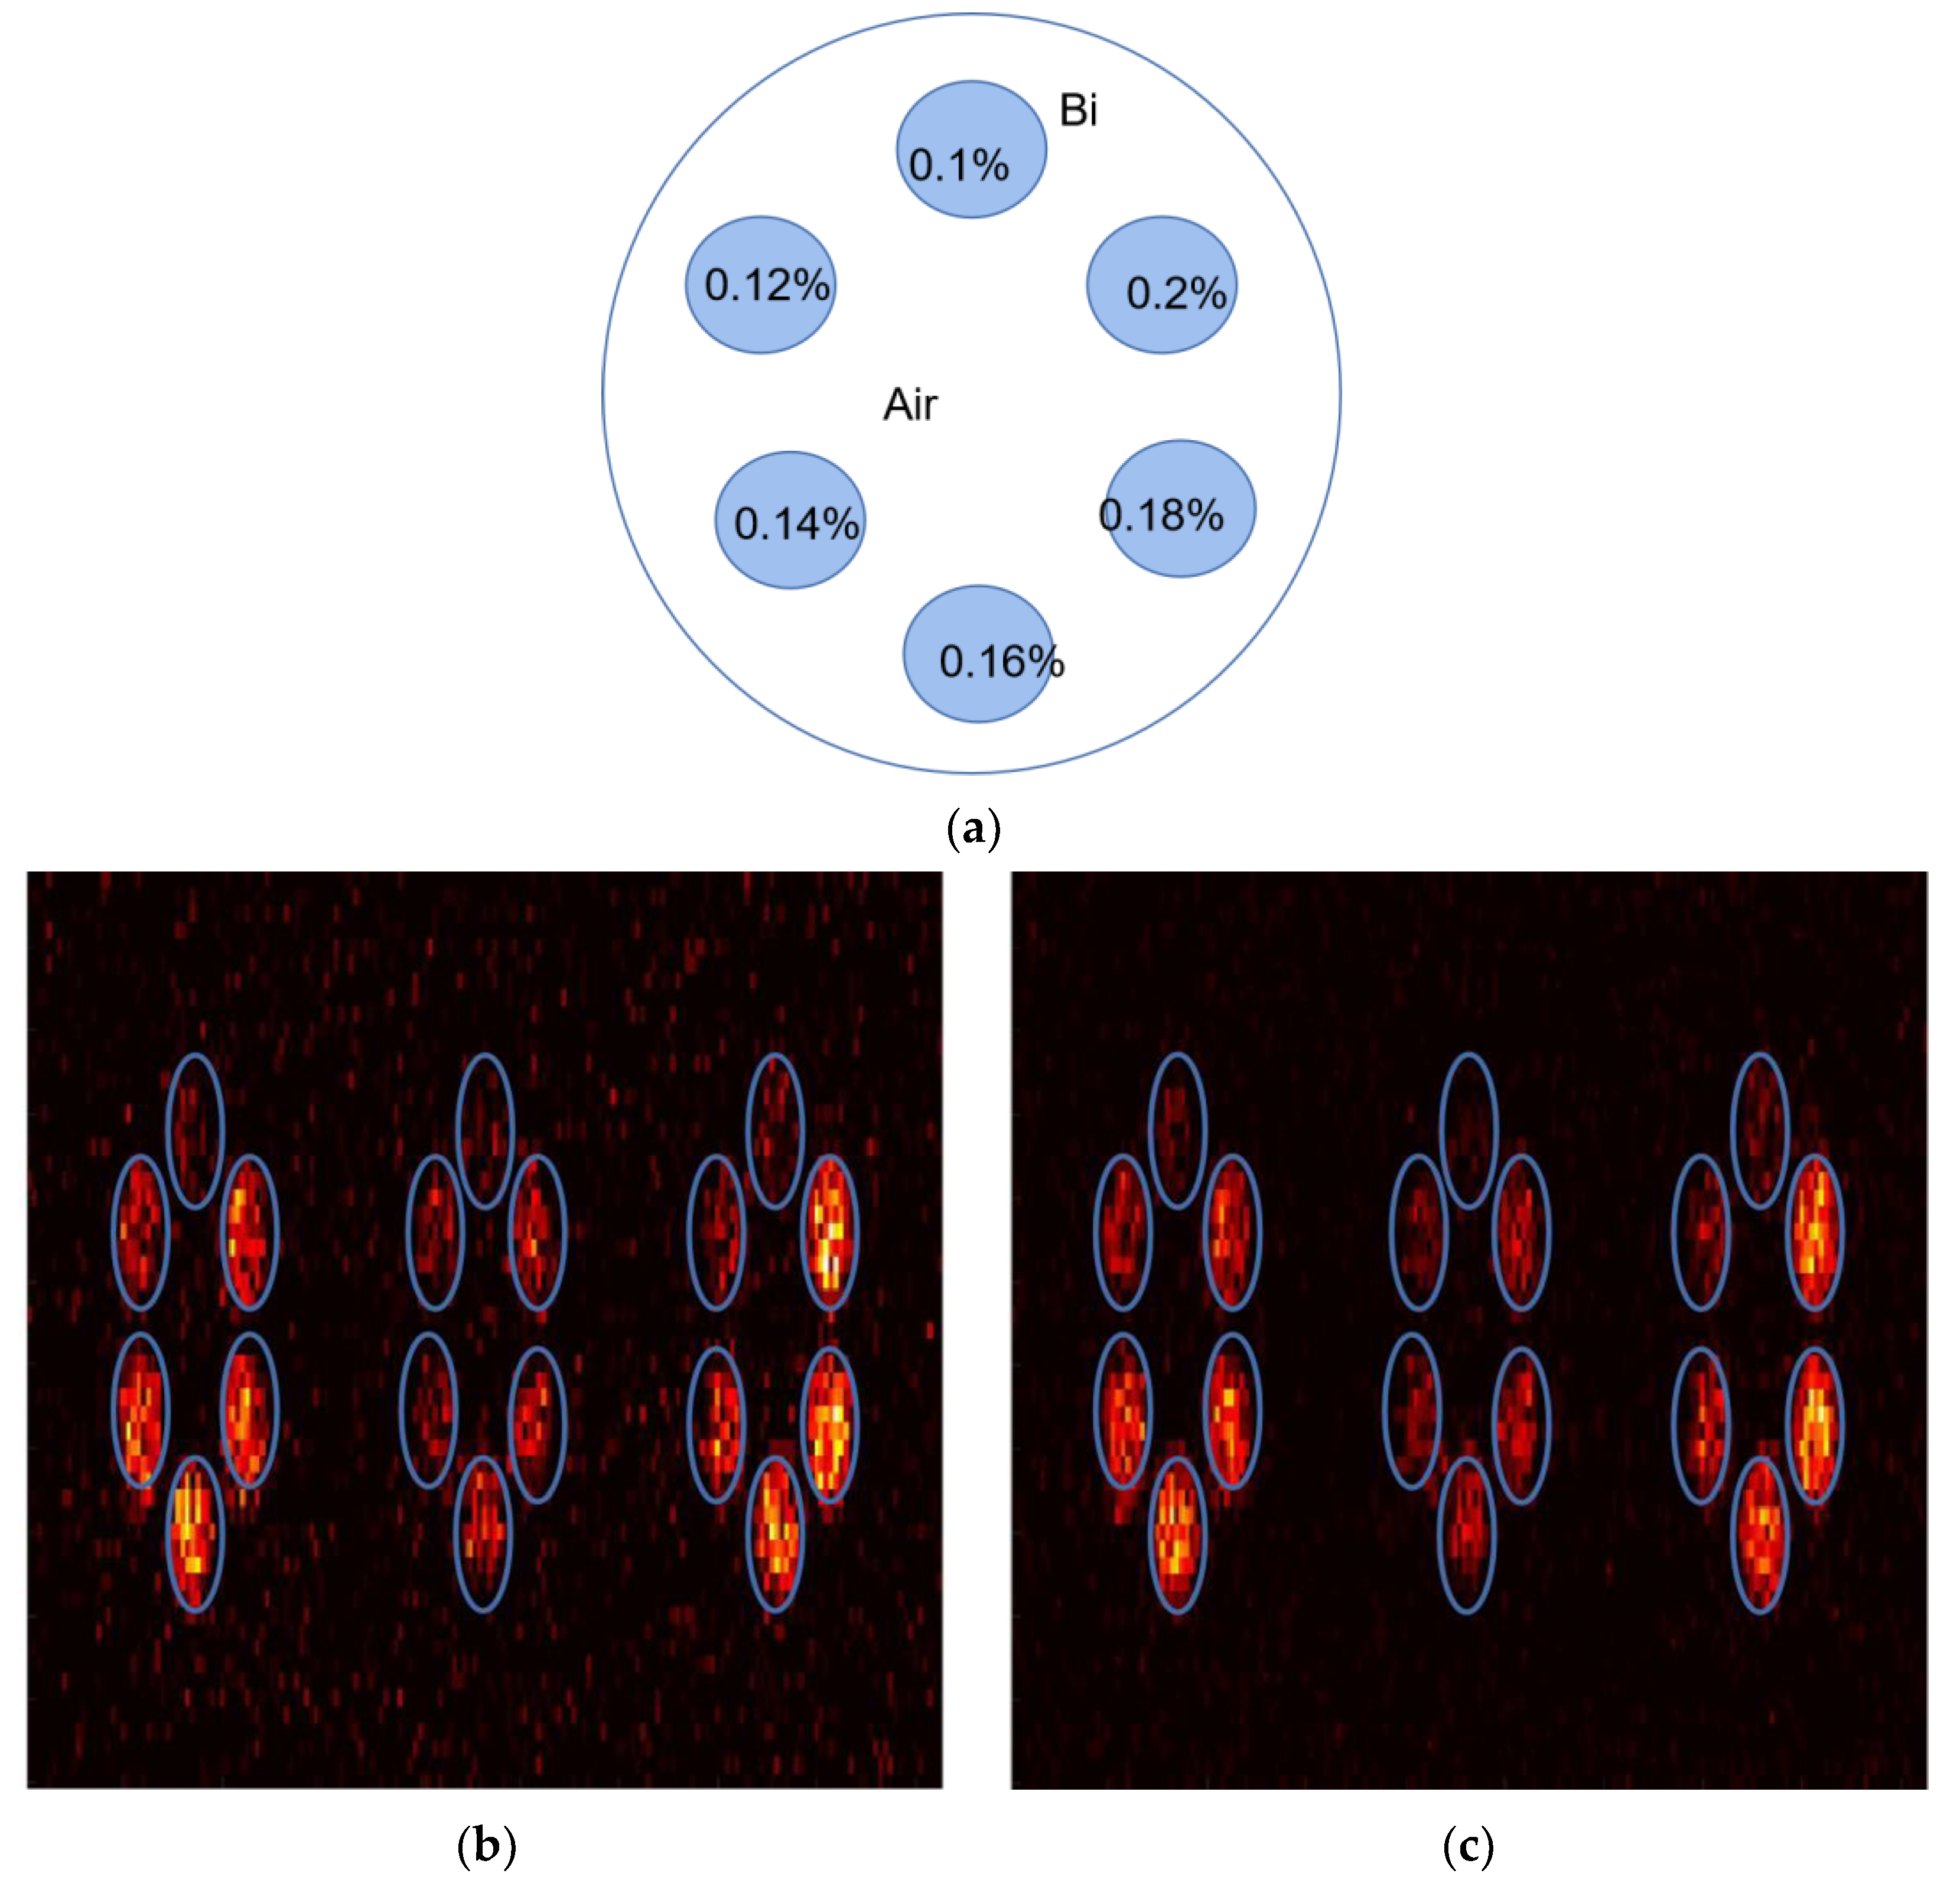

2.3. Datasets

3. Results

4. Discussion